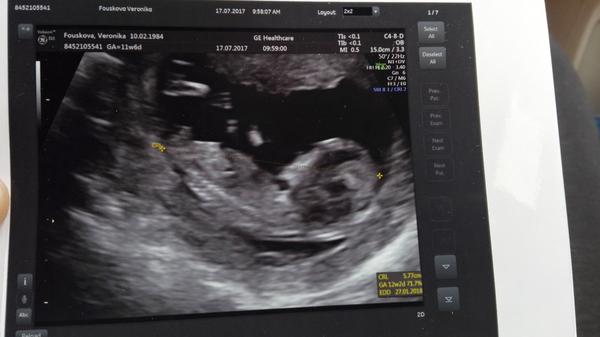

@vvercatkoo

Krasna fotecka, ja jdu po delsi dobe az 1.8. na screening a mam strach, aby vse bylo zase v poradku a mela taky aktivku jako ty :*.